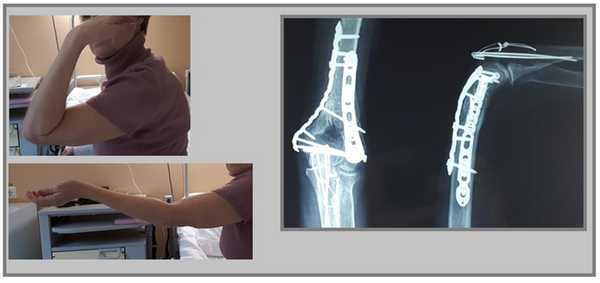

В случае настолько грубого смещения при первичном осмотре целесообразно выполнить анестезию перелома и устранить смещение с фиксацией конечности в задней гипсовой лонгтеной повязке. После обследования и предоперационной подготовки пациентка взята в операционную. Выполнен остеосинтез при помощи пластин с угловой стабильностью Synthes.

Послеоперационные рентгенограммы показывают, что смещение отломков полностью устранено, нормальные взаимоотношения костей верхней конечности восстановлены.

В ходе операции необходимо оценивать стабильность остеосинтеза к движениям в суставе, так как послеоперационный протокол предполагает раннюю нагрузку уже через 1-2 дня после операции. Ранние движения в суставе препятствуют образованию грубых рубцов и спаек, которые в противном случае могут вызвать стойкое ограничение движений в суставе.